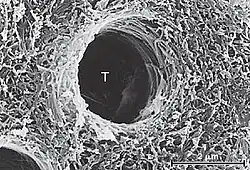

It can be accomplished by either etch-and-rinse (total etch) or self-etch adhesives. In etch-and rinse, acid will dissolve the minerals to a certain depth and leaves the highly porous dentinal collagen network suspended in water. Then, the collagen network is infiltrated with resin monomers. After chemical polymerization of these monomers happen, activated by light cure, it will result in a polymer-collagen biocomposite, commonly known as the hybrid layer:[4]

- Primer and bonding resin are applied to etched dentin, they penetrate the intertubular dentin, forming hybrid layer.

- They also penetrate and polymerize in open dentinal tubules, forming resin tags.

Its presence was identified by Nakabayashi and co-workers where the hybrid layer consists of demineralized intertubular dentin and infiltrated and polymerized adhesive resin.[6]

The hybrid layer is hydrophobic, acid resistant and tough. The quality of hybrid layer formed decides the strength of resin dentin interface. When the hybrid layer becomes thicker and more uniform, the bond strength is better.[6]

Smear layer will fill the orifices of the dentinal tubules, hence forming smear plugs. These smear plugs decrease dentin permeability by 90% and the smear plug alone can prevent adhesive resin penetration into dentinal tubules. The thickness of smear layer can range from 0.5-2 μmeter and for the smear plug, 1 to 10 μmeter.[5]